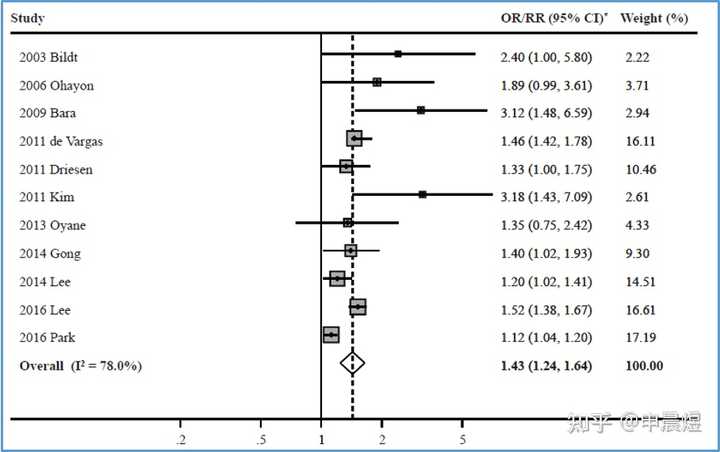

熬夜与抑郁症之间存在相关关系,而且可能互为因果。

生物节律紊乱使抑郁症风险升高

睡眠和生物节律紊乱(SCRD)是21世纪普遍特征,对轮班工人的研究表明,SCRD不仅导致认知障碍,还会导致代谢综合征和抑郁症等精神障碍[3]。

生物节律紊乱引发的睡眠障碍持续存在,可导致抑郁复发风险增高[4]。

与昼夜节律正常的同龄人相比,节律延迟的个体抑郁症状更严重,且更易出现轻度躁狂症状[5]。